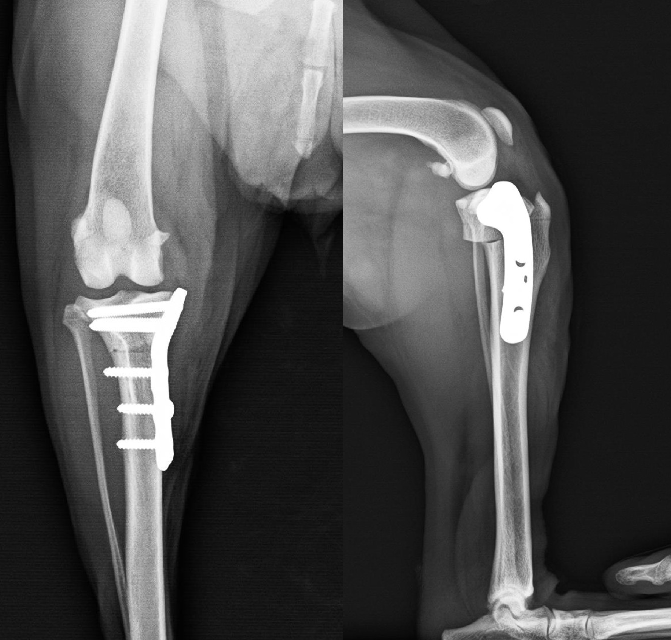

TPLO(脛骨高平部水平骨切り術)

膝下の脛骨を扇状に切断し、尾側に移動することで関節内の脛骨と大腿骨を正常な位置に戻し特殊なプレートで固定します。

大腿骨と脛骨の位置関係が整復されることで負重する時の膝の動きが安定化して跛行が改善します。

【術前】大腿骨遠位端骨折プレート整復固定 -

【術後】大腿骨遠位端骨折プレート整復固定 -